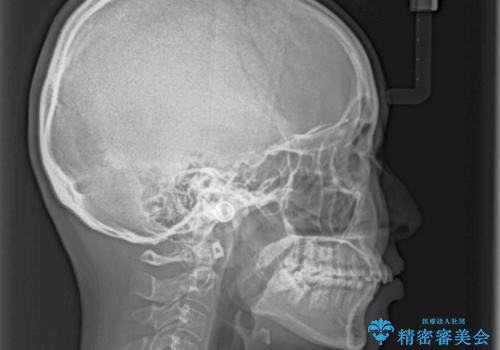

歯列全体の拡大とIPR(歯と歯の間を削る)によってデコボコが解消するようにし、さらにゴムかけを活用して右側の咬み合わせ位置を変えるように設計し、インビザラインにより治療を行うこととしました。

後方移動に際し、上下顎の親知らずは3本とも抜歯することとしました。